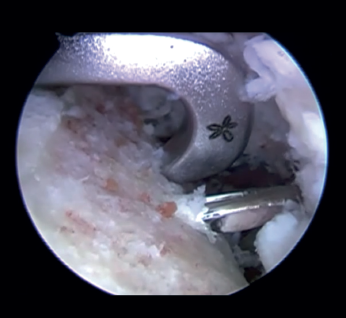

Introduction of the glenoid guide and positioning of the sheaths

(Figures 2 and 3)

Figure 2. View from the anterosuperior portal (left shoulder). Note the glenoid guide positioned at the centre of the defect and drilling at its upper and lower portion, spaced 10 mm apart.

Arthroscope is introduced through the anterosuperior portal, and the glenoid guide is introduced through the posterior portal, and passed paralel to the glenoid surface until the hook is located at the centre of the bone defect. The guide is secured with two cannulas inserted through two small accessory incisions, until connecting with the posterior cortical layer. Both cortical layers are drilled through them using a 2.8 mm drill fitted with a sheath so that on withdrawing the drill the sheath is positioned at drilling level. This step is made twice to introduce two sheaths: one above and the other below the glenoid guide hook and spaced 10 mm apart. Through these sheaths we advance two monofilament loops that are retrieved sequentially through the anterior portal for subsequent passing of the graft. At this point we can remove both sheaths and the glenoid guide, taking care to prevent the guide hook from coming into contact with the glenoid surface in order to avoid damaging to the cartilage.